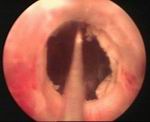

In this procedure, a thin telescope is passed into the urethra to see exactly where the stricture is. This is done during a general anaesthetic. A tiny knife is then passed down the telescope to cut along the stricture. This widens the narrowed stricture. You will get some relief of symptoms from this procedure. About one case in three is cured for good. However, like dilation, the stricture may re-form and the procedure may have to be repeated from time to time in some cases.